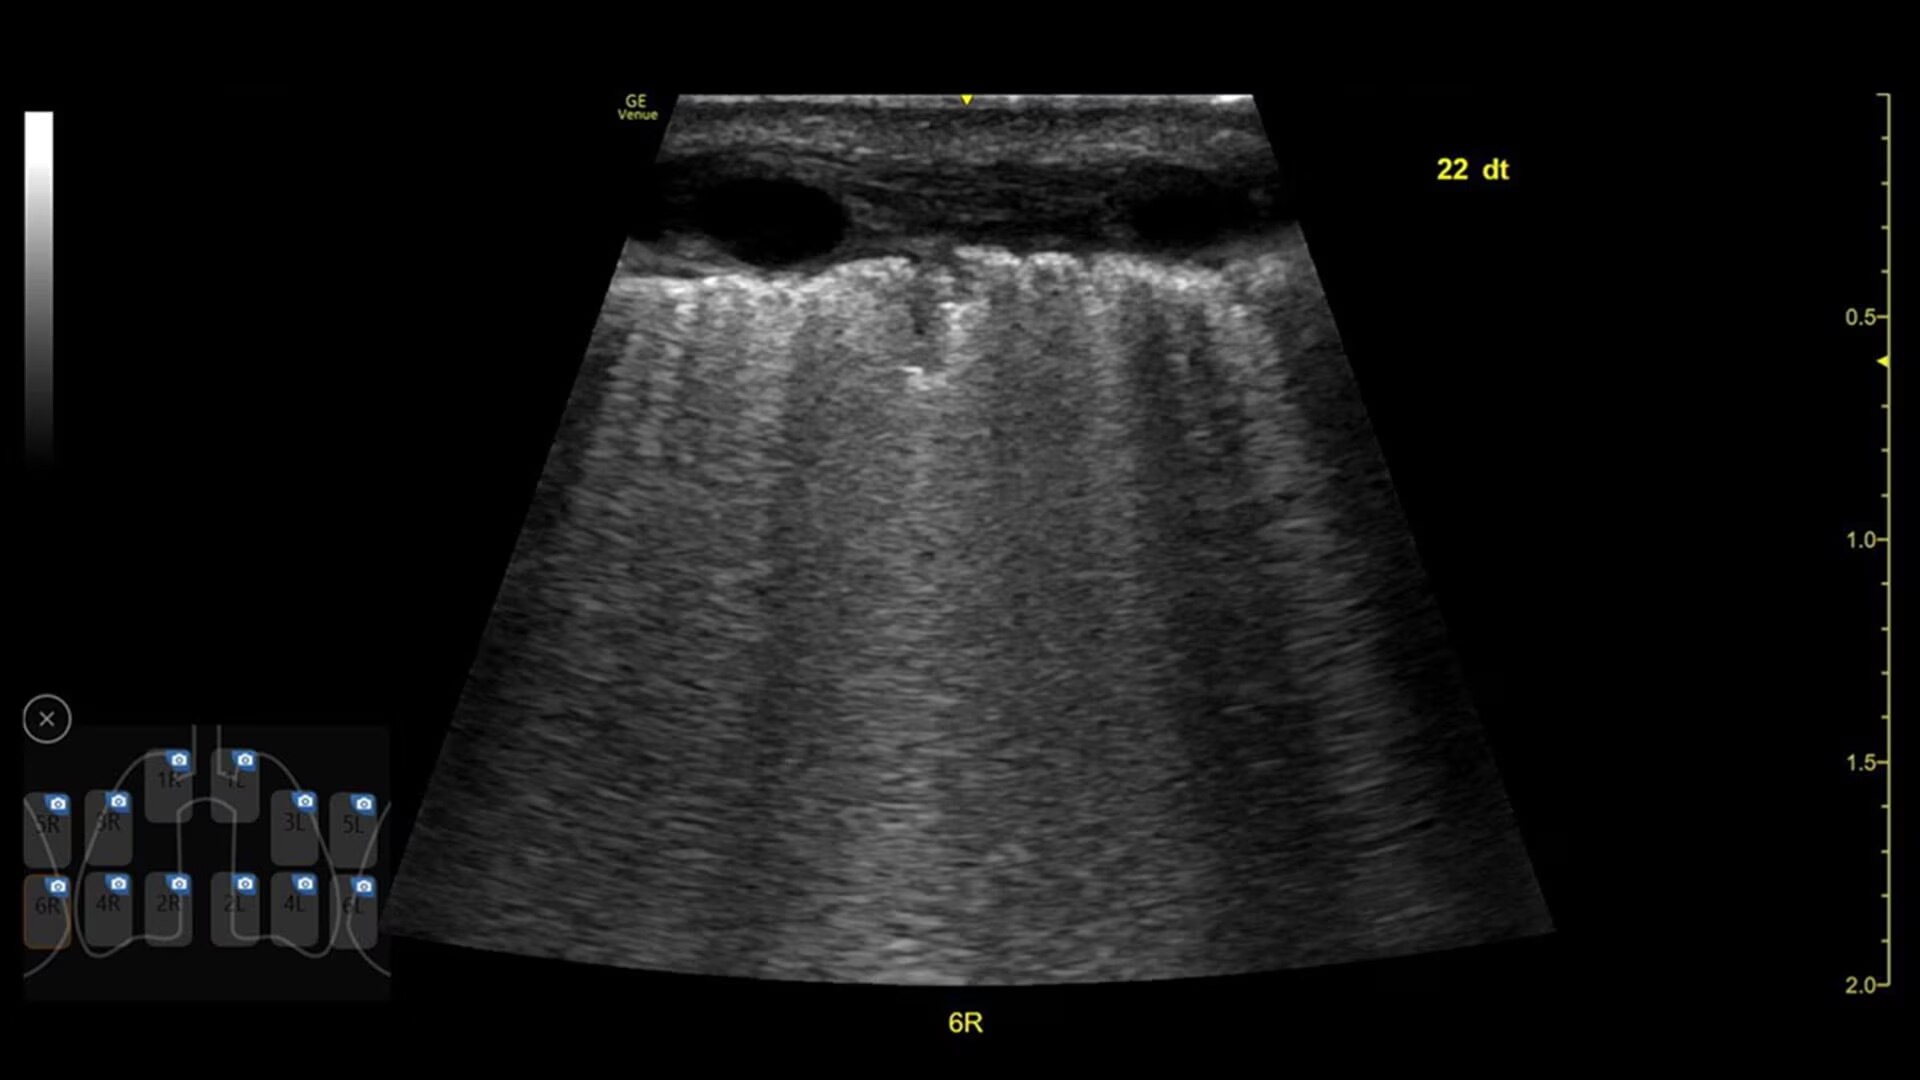

Review lung segment images in one view with Lung Diagram

A single view diagram of anatomical lung segments with one click image storing. Keeps track of segmental lung assessment and can be helpful in showing trends in response to therapy.